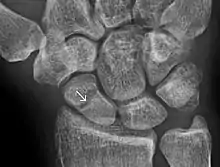

- Jarraya, Mohamed; Hayashi, Daichi; Roemer, Frank W.; Crema, Michel D.; Diaz, Luis; Conlin, Jane; Marra, Monica D.; Jomaah, Nabil; Guermazi, Ali (2013). "Radiographically Occult and Subtle Fractures: A Pictorial Review". Radiology Research and Practice. 2013: 1–10. doi:10.1155/2013/370169. ISSN 2090-1941. PMC 3613077. PMID 23577253. CC-BY 3.0